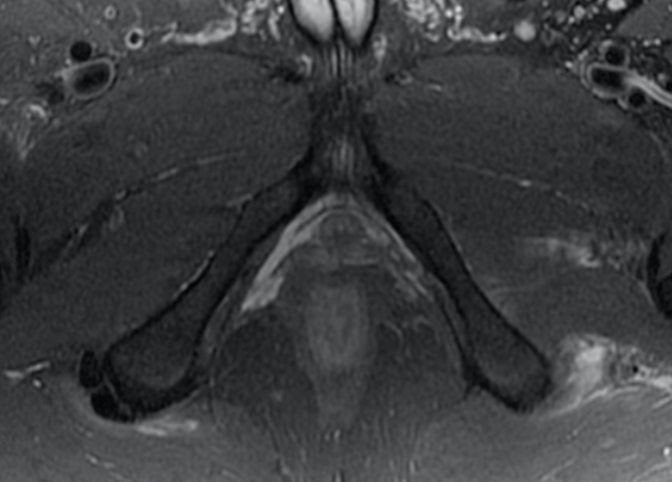

A 21-year-old female presents to the emergency room after falling from dancing on a table and injuring her right ankle. She is in severe pain and unable to bear weight comfortably with swelling and tenderness along the lateral malleolus. X-rays are taken and shown above.